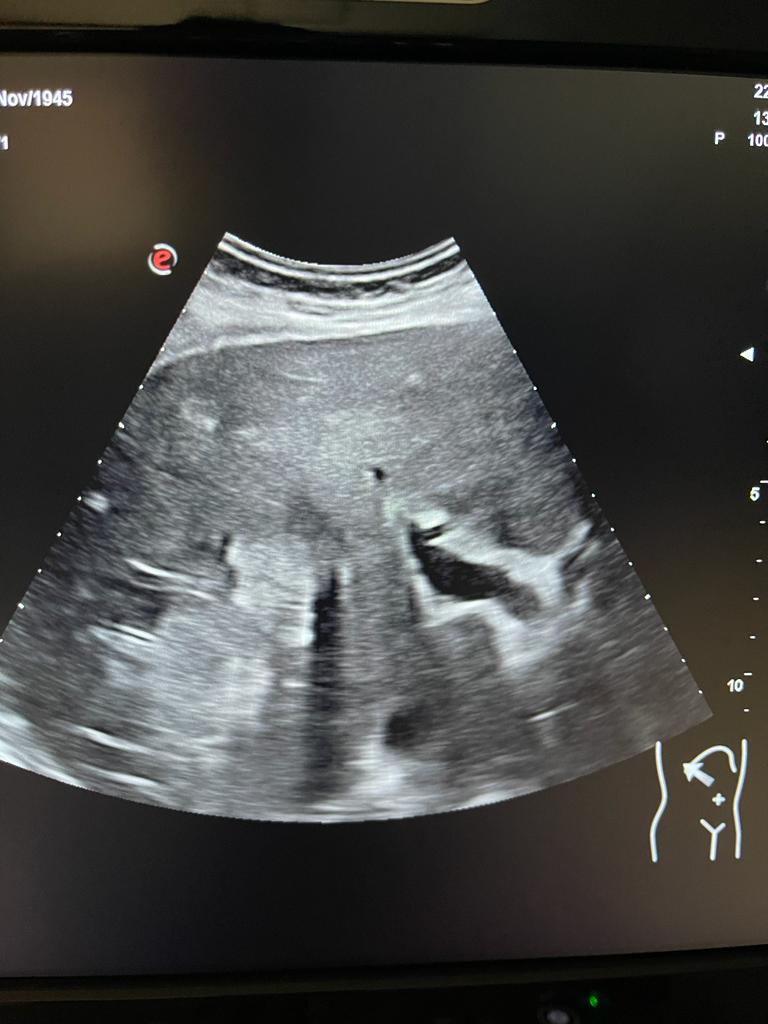

Se aprecia hígado heterogéneo con múltiples LOES hepáticas hiperecogénicas (una de ellas de unos 7x7 cm), sin captación de doppler. Al menos otras 2 LOES de menor tamaño presentan halo hipoecoico. Vesícula replecionada de contornos lisos y sin litiasis en su interior. Ambos riñones visualizados de tamaño normal y sin datos de hidronefrosis.